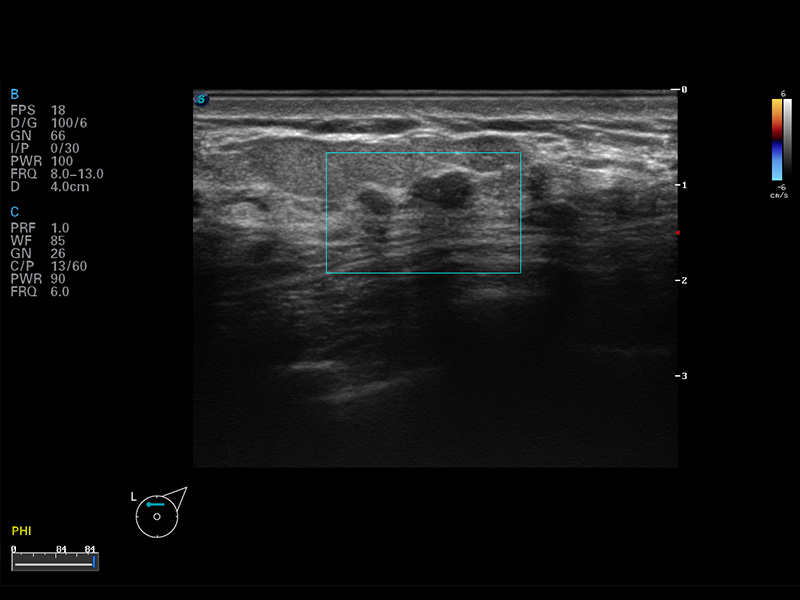

μ-Scan微米成像